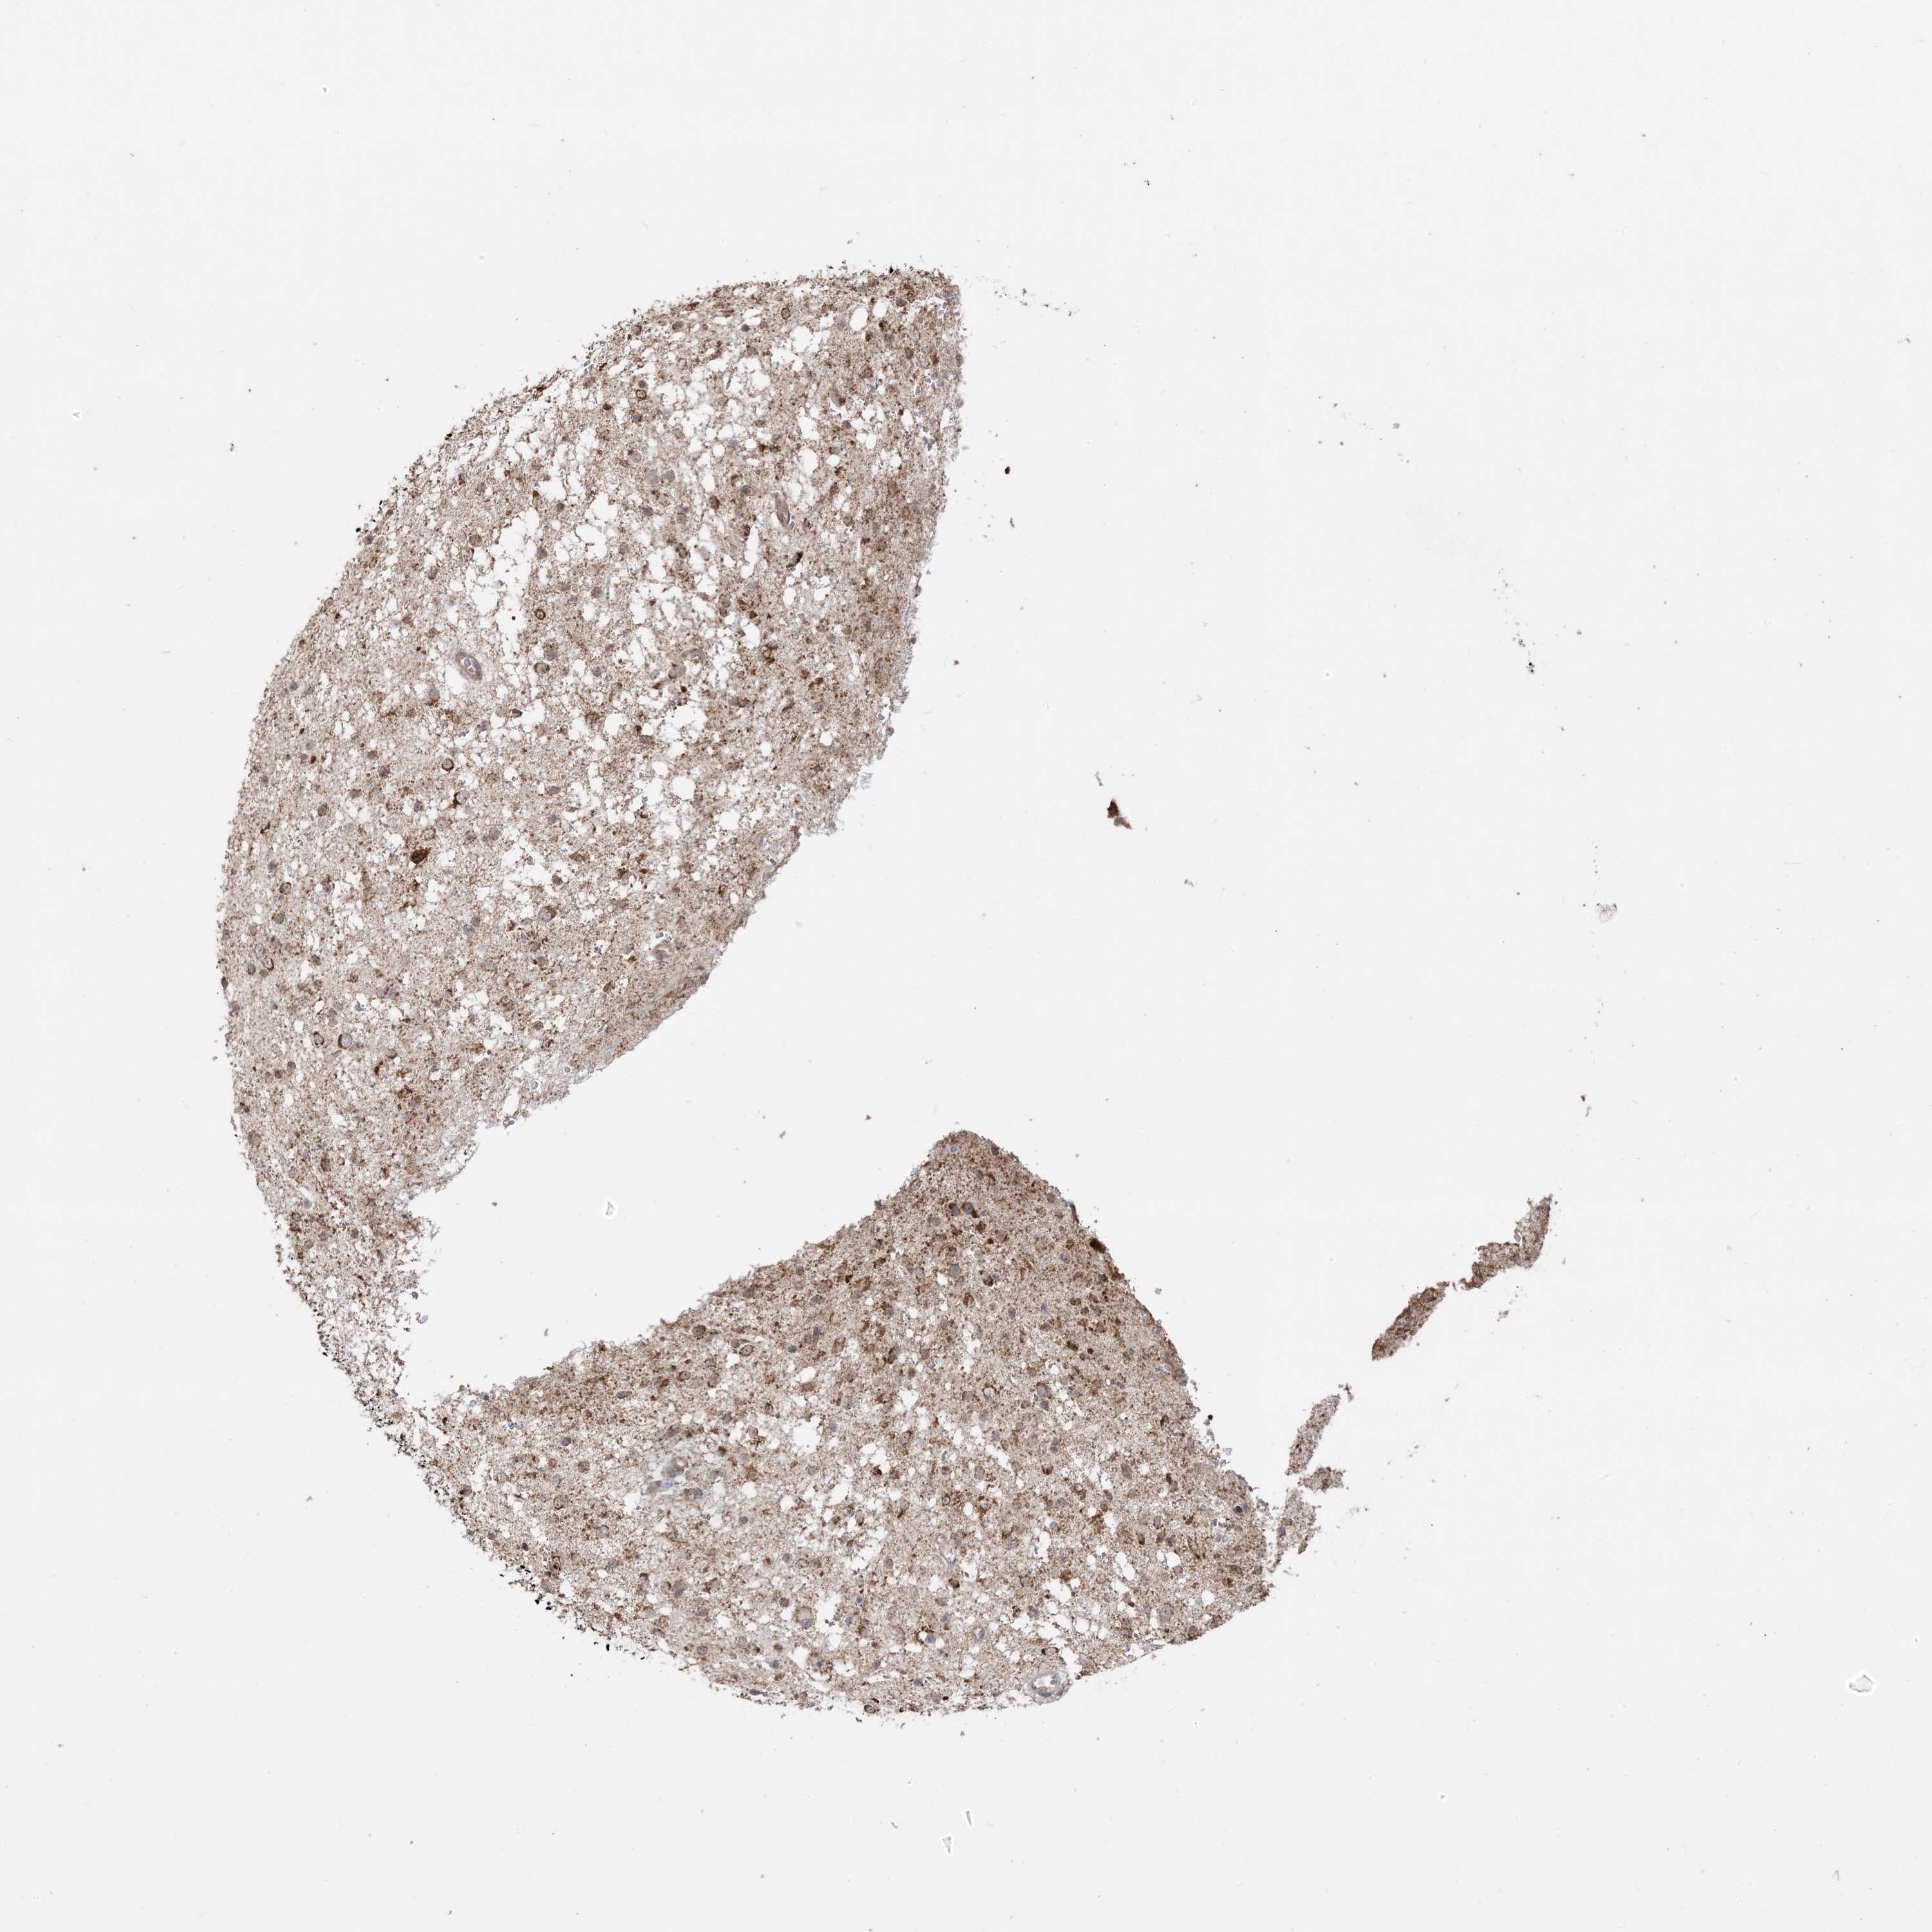

GLIOMA - Protein expressioni

A mouse-over function shows sample information and annotation data. Click on an image to view it in a full screen mode. Samples can be filtered based on level of antibody staining by selecting one or several of the following categories: high, medium, low and not detected. The assay and annotation is described here.

Note that samples used for immunohistochemistry by the Human Protein Atlas do not correspond to samples in the TCGA dataset.

Antibody stainingi

Antibody staining in the annotated cell types in the current human tissue is reported as not detected, low, medium, or high, based on conventional immunohistochemistry profiling in selected tissues. This score is based on the combination of the staining intensity and fraction of stained cells.

Each image is clickable and will lead to virtual microscopy that enables deeper exploration of all samples and also displays staining intensity scores, fraction scores and subcellular localization as well as patient and tissue information for each sample.

Antibody CAB037142

Staining

High

Medium

Low

Not detected

Intensity

Strong

Moderate

Weak

Negative

Quantity

>75%

75%-25%

<25%

None

Location

Nuclear

Cytoplasmic/membranous

Cytoplasmic/membranous,nuclear

Glioma, malignant, High grade

Glioma, malignant, Low grade